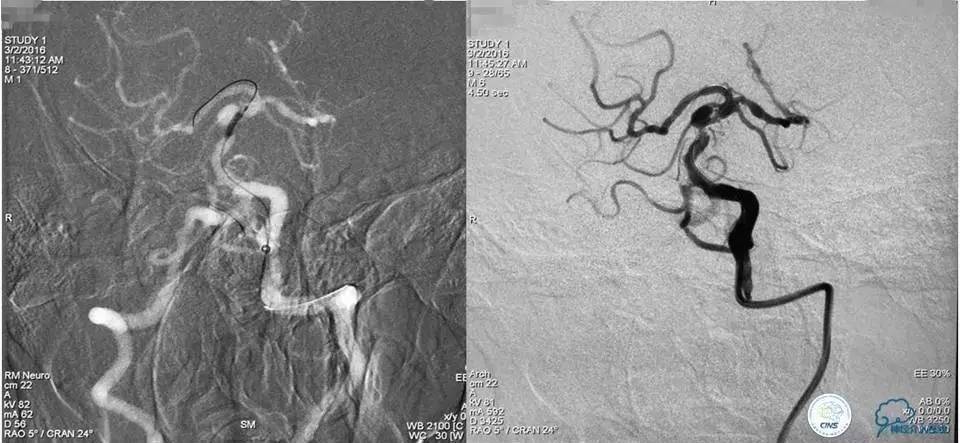

入院后DSA检查:

造影显示:基底动脉重度狭窄,狭窄率90%;基底动脉动脉瘤,大小6.71mm×3.55mm,瘤颈宽为4.51mm。

血管内治疗策略:同样经球囊扩张基底动脉狭窄处,然后采用顺序式操作方式先释放Enterprise支架1枚覆盖瘤颈及支撑血管狭窄处,再结合弹簧圈栓塞动脉瘤。

手术经过如下:

路径图下沿导引导管送入TRANSEND微导丝(0.014″长度300cm)小心通过狭窄段至左侧大脑后动脉P3段,沿微导丝送入Gateway球囊(2mm×22mm)至狭窄段,准确定位后球囊逐渐加压至7atm,可见球囊完全张开,快速抽瘪球囊,造影显示狭窄段较前明显改善,残余狭窄率约70%,考虑到球囊扩张后仍有较高残余狭窄,为防止弹性回缩导致再狭窄及血栓形成,尽快行支架置入术。

撤出球囊,沿微导丝送入ENTERPTISE (4.5mm×22mm)自膨式支架至狭窄段,准确对位后成功释放支架,造影显示双椎动脉颅内段及基底动脉前向血流好,支架贴壁良好,动脉夹层消失,残余狭窄约30%。支架释放完成后,微导管经支架网眼导入瘤腔内,送入弹簧圈数枚并解脱。手术结果如下:

术后工作位造影

术后右斜位和左斜位造影显示动脉瘤完全栓塞